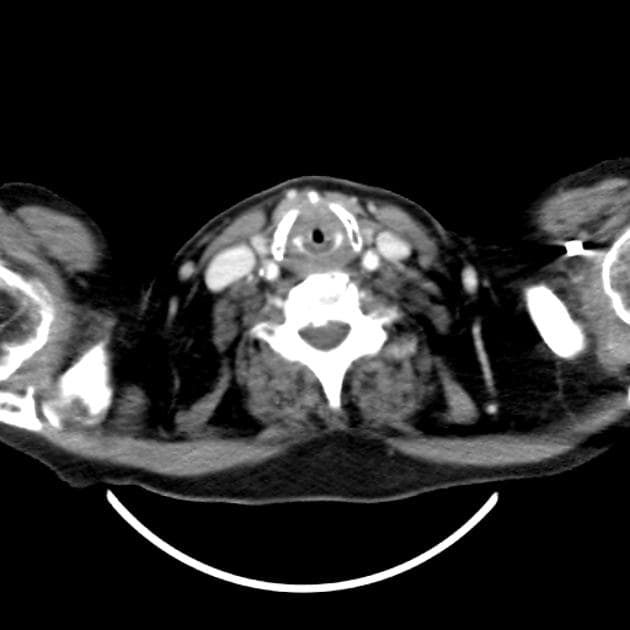

Axial C+ arterial phase

Dày thành thành mạch lan tỏa, dạng vòng quanh, lan rộng từ hầu họng, hạ họng và toàn bộ thực quản (quan sát thấy trên hình ảnh mặt cắt dọc và mặt cắt ngang), chèn ép rõ rệt vào lòng thực quản. Tổn thương cũng lan đến thanh quản với hiện tượng dày niêm mạc rõ rệt làm mất lòng thanh quản. Có hiện tượng dày mô mềm xung quanh vùng quanh họng và quanh thực quản, đồng thời thấy mờ các khe gian mỡ.

- "Chẩn đoán hình ảnh có thể ghi nhận hiện tượng dày thành vòng quanh thực quản và vùng hạ họng - thanh quản kèm hẹp lòng, giống với các bệnh viêm hoặc tổn thương khối u."